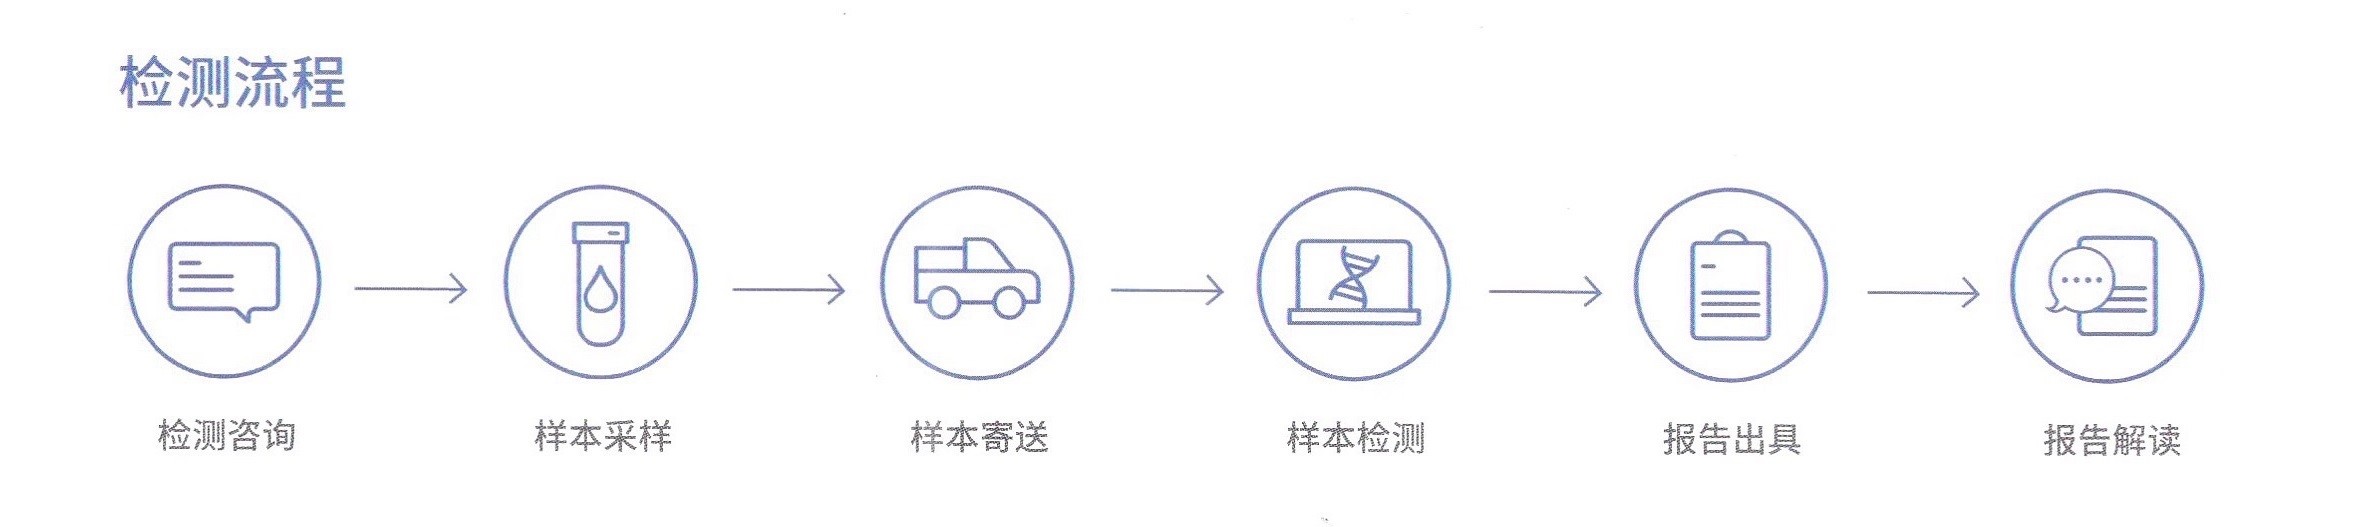

检测周期

组织样本:6个自然日;血液样本:5个自然日。

样本类型

手术/穿刺组织石蜡贴片、手术/穿刺新鲜组织、石蜡包埋组织、外周血。